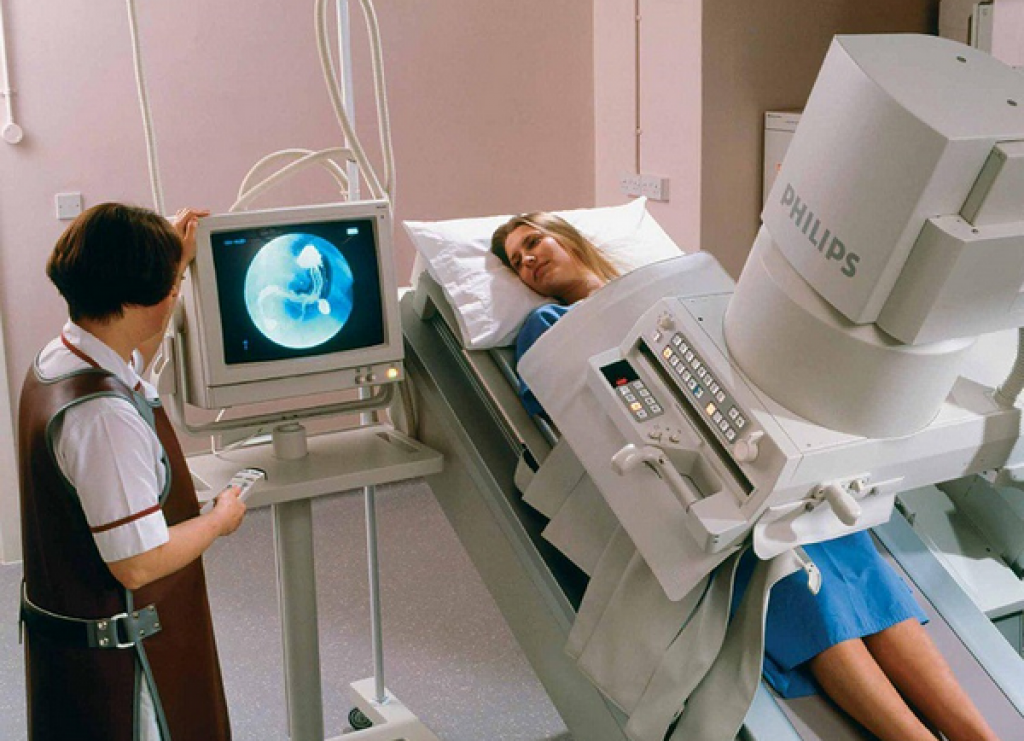

Рентгеноконтрастные Исследования Кишечника: Визуализация и Методики

Раздел: Иллюстрированный журнал